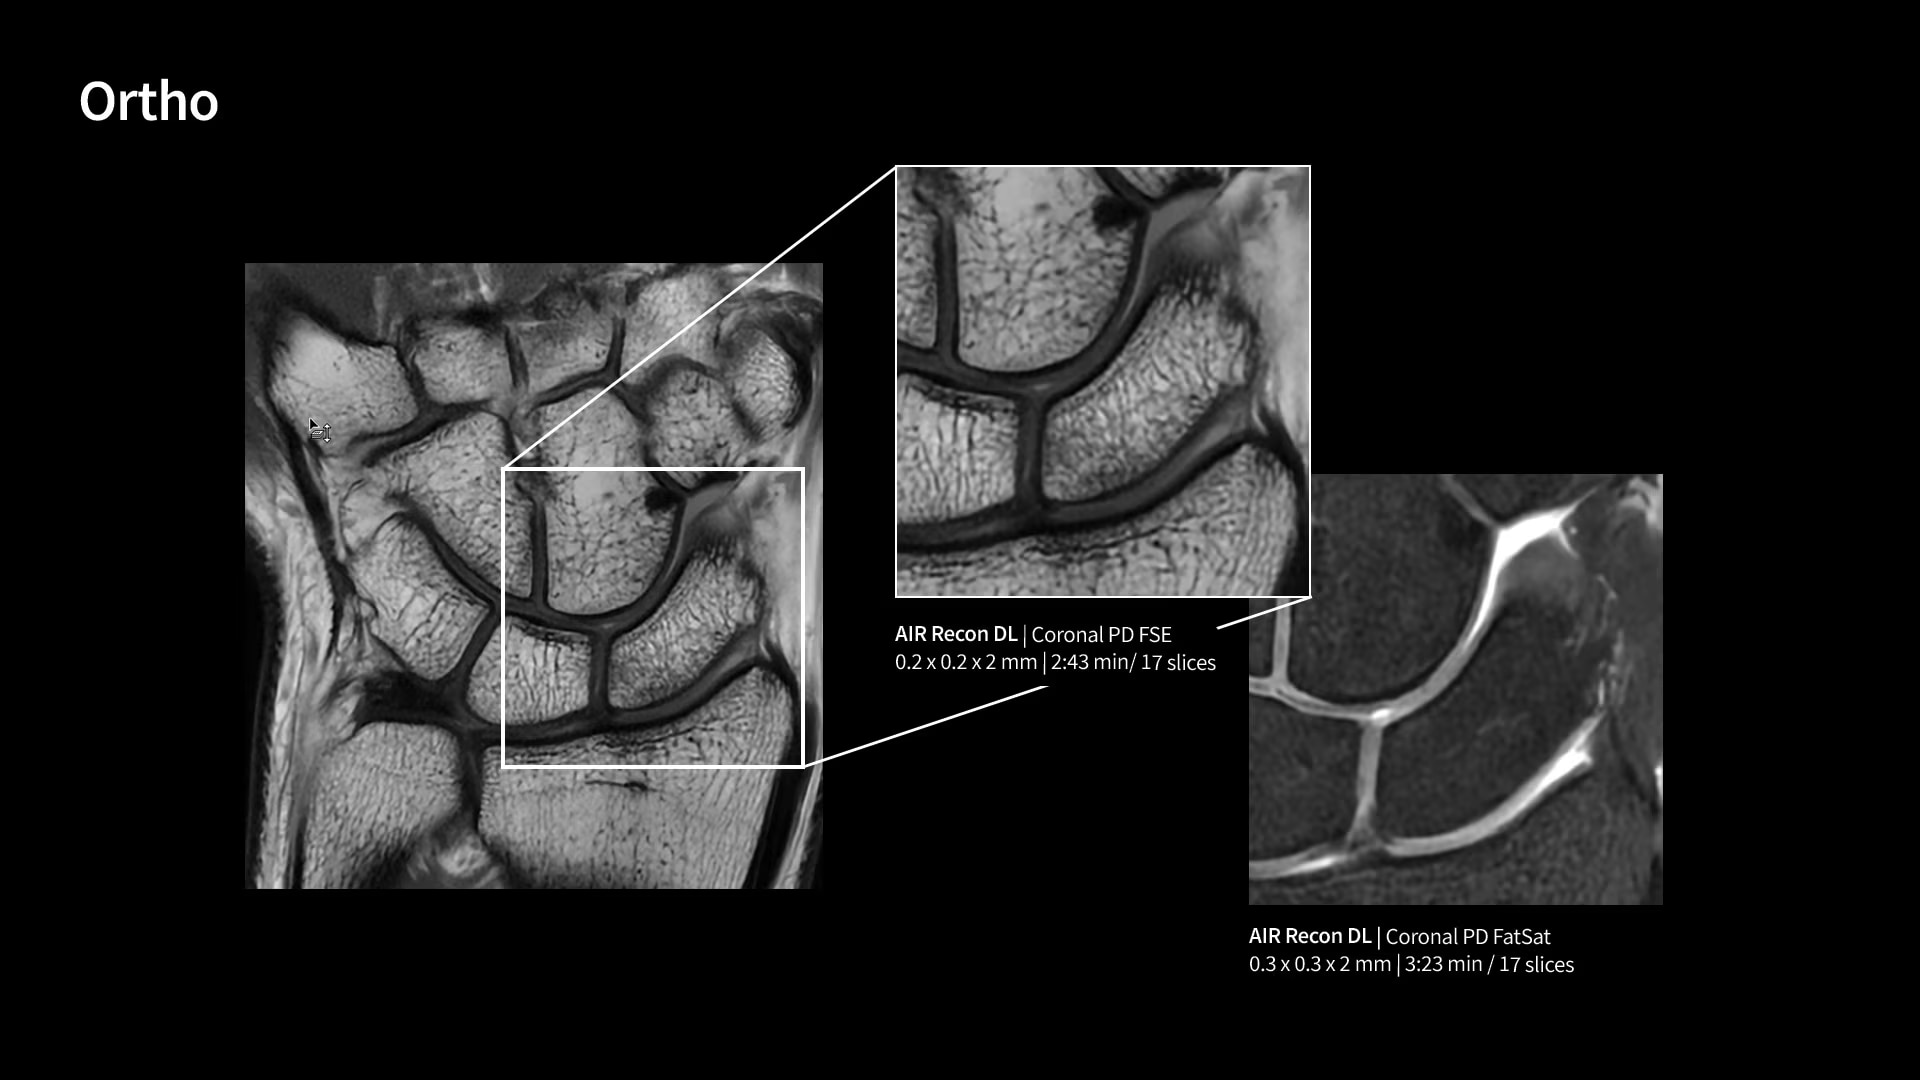

Unlock your potential

With GE HealthCare's comprehensive suite of deep-learning solutions integrated into SIGNA Sprint, you can unlock the full potential of your MRI system. No need for complicated patient setups or imaging protocols. The exceptional intelligence of our AI solutions offer multiple benefits, with AIR Recon DL giving pin-sharp images, Sonic DL accelerating scans up to 12x, and AIR x enabling automated slice placement. All helping to enhance your department’s workflow efficiency, increase patient throughput, and get the diagnostic clarity you need, faster.¹ Meaning you can spend more time on what truly matters—personalized patient care, enabling optimized treatment plans and treatment response monitoring—ultimately, supporting better clinical outcomes.